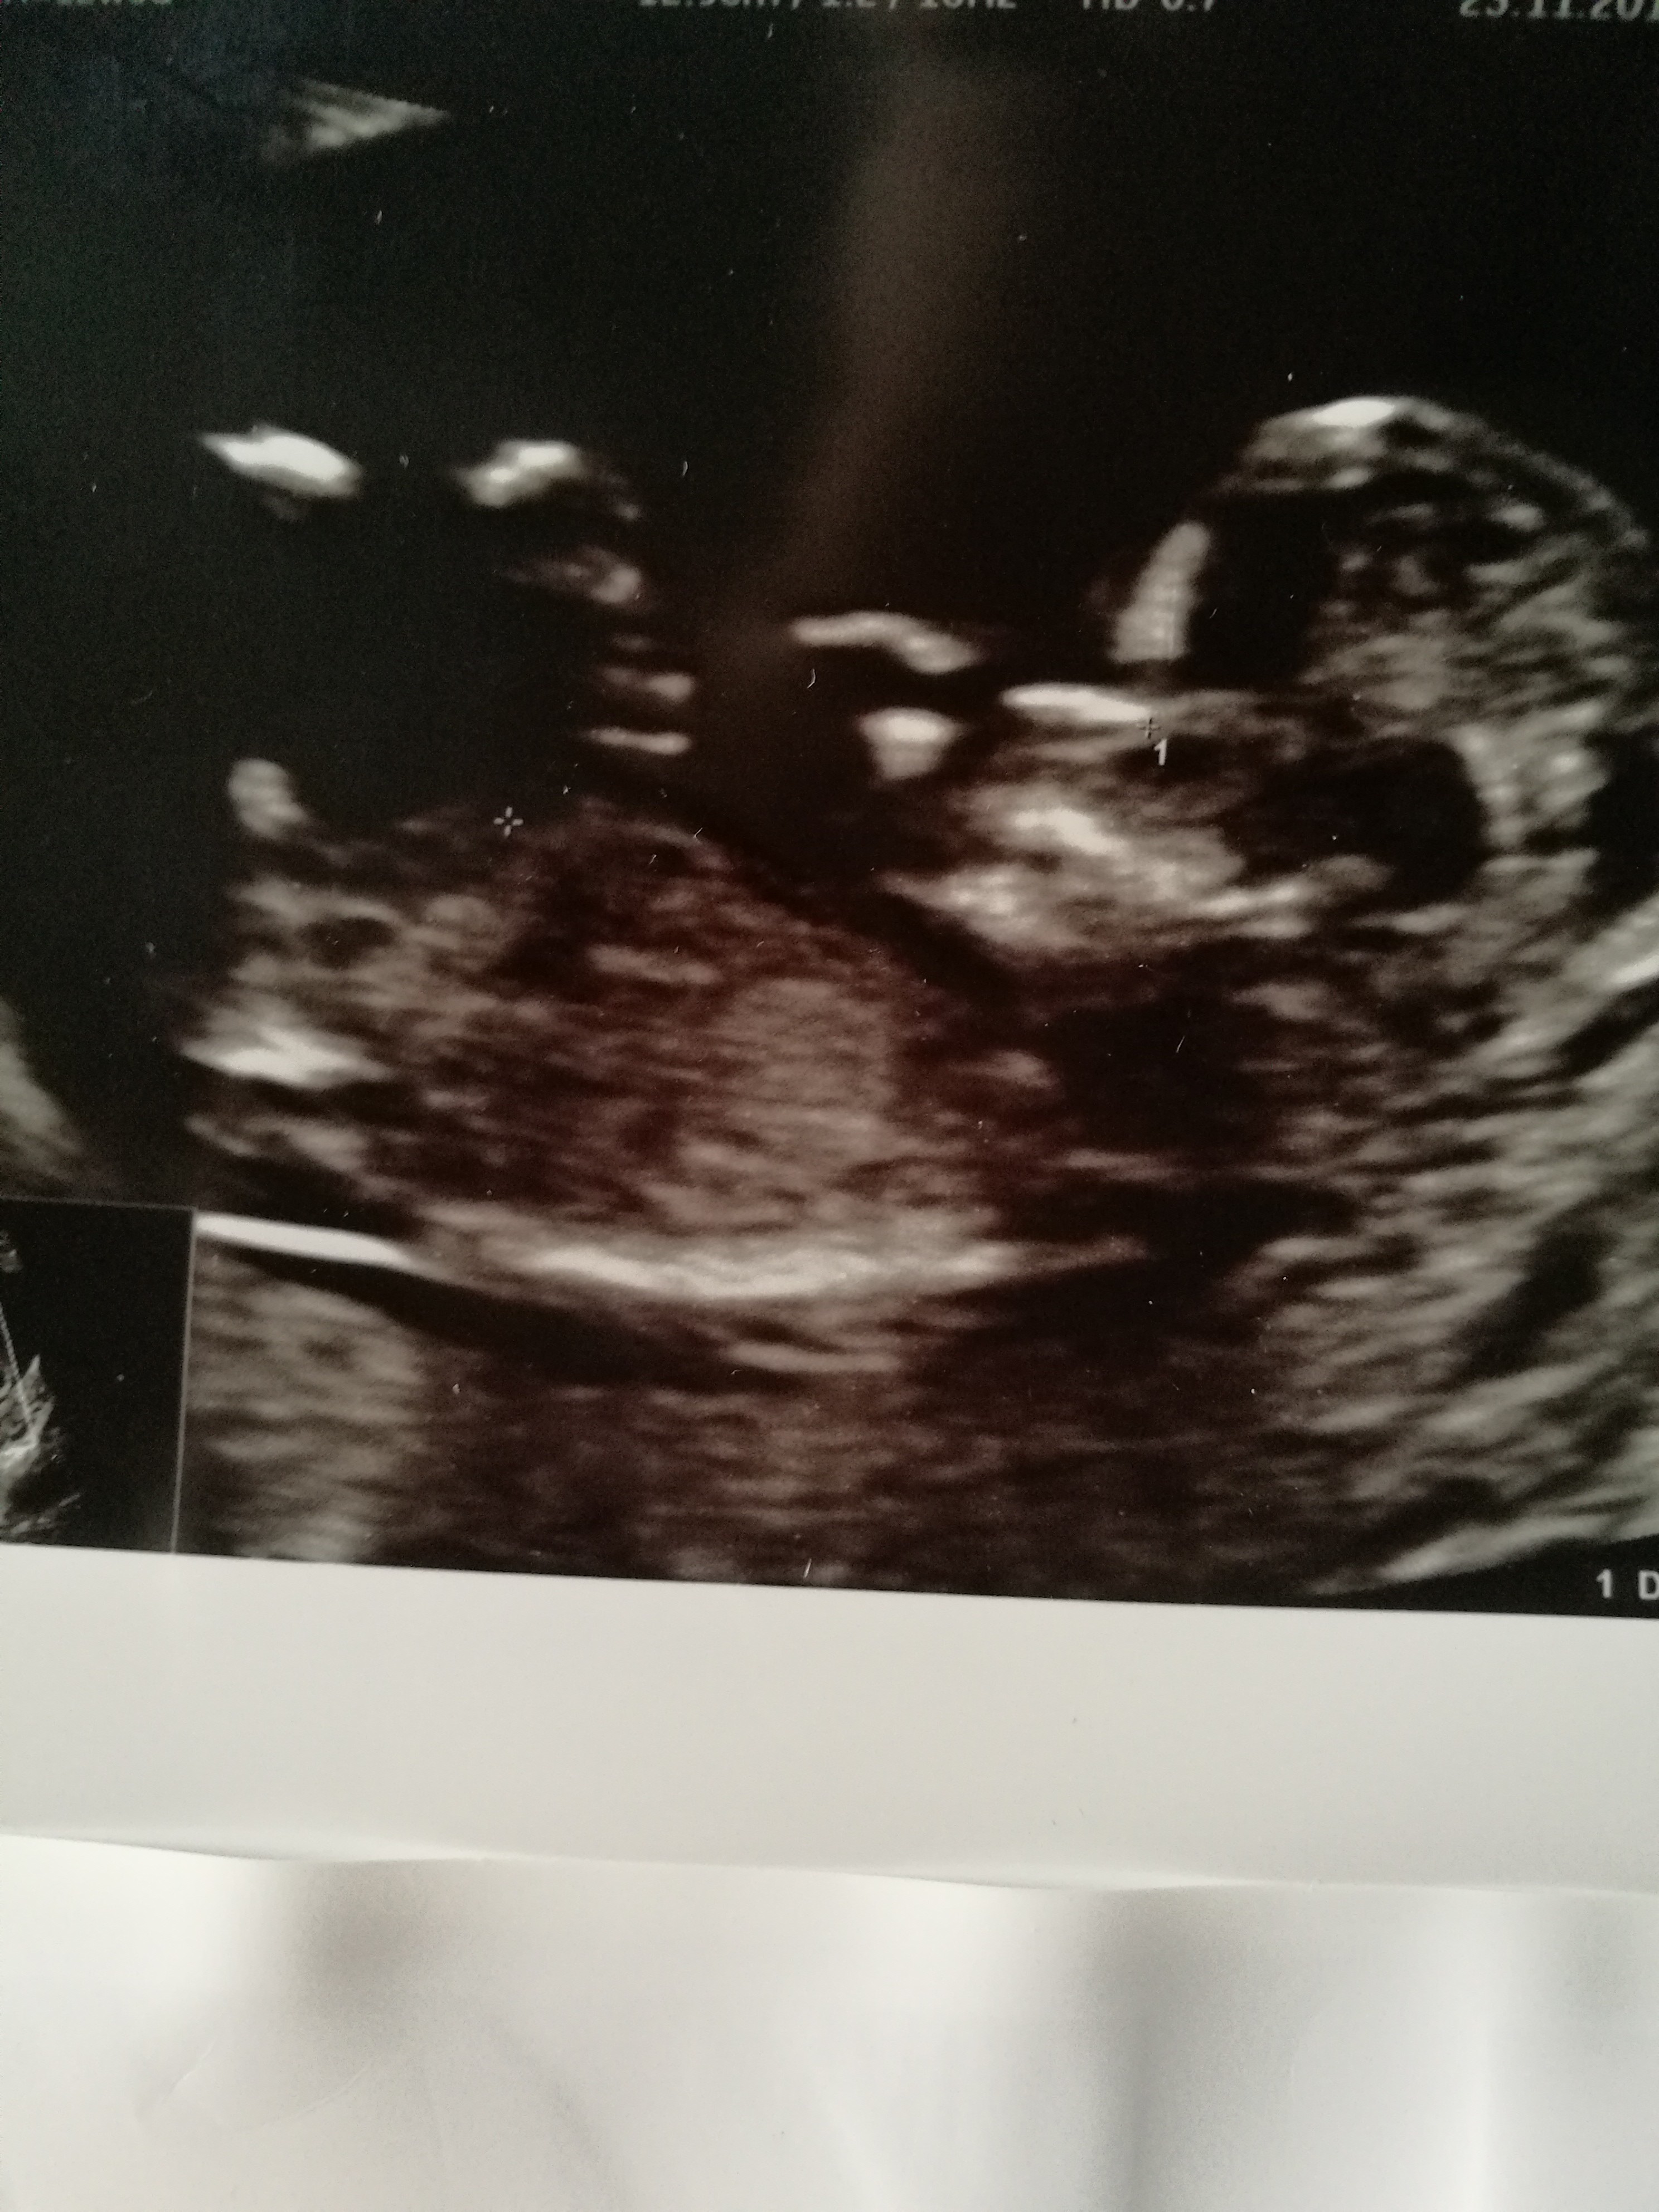

Cześć dziewczyny. Co sądzicie o moich zdjęciach? W 11tc5dc pierwsze zdj-lekarz stwierdził że na 75prc. dziewczynka. Tydzien później jeszcze raz byłam u niego, bo jeszcze musiał coś podejrzeć i w 12tc5d następne zdjęcia-powiedział że dziś na 75 prc. chłopak. Powiedział ogólnie że daje 50proc i trzeba poczekać do połówkowego. Czy ktoś miał tak szybką zmianę płci. Zdjęcia z obydwu badań wydają się jednoznaczne: na pierwszym dziewczynka, na drugim chłopiec. Czy już zostanie chłopiec?? Czy jest szansa że się zmieni? Ktoś tak miał? Dałybyście 100proc chłopak, czy jakąś nadzieję na dziewczynkę? Lekarz uznał, że jest jakiś procent kobiet u których się to zmienia, nie wiem co miał na myśli.

Za wczesnie lekarz ocenil plec pierwszym razem dlatego ze nub do 13 tc moze sie podniesc ...na poczatku wszystkie nuby sa dziewczynkowe.Raczej nastawialbym sie na chlopca ale poczekaj na polowkowe.